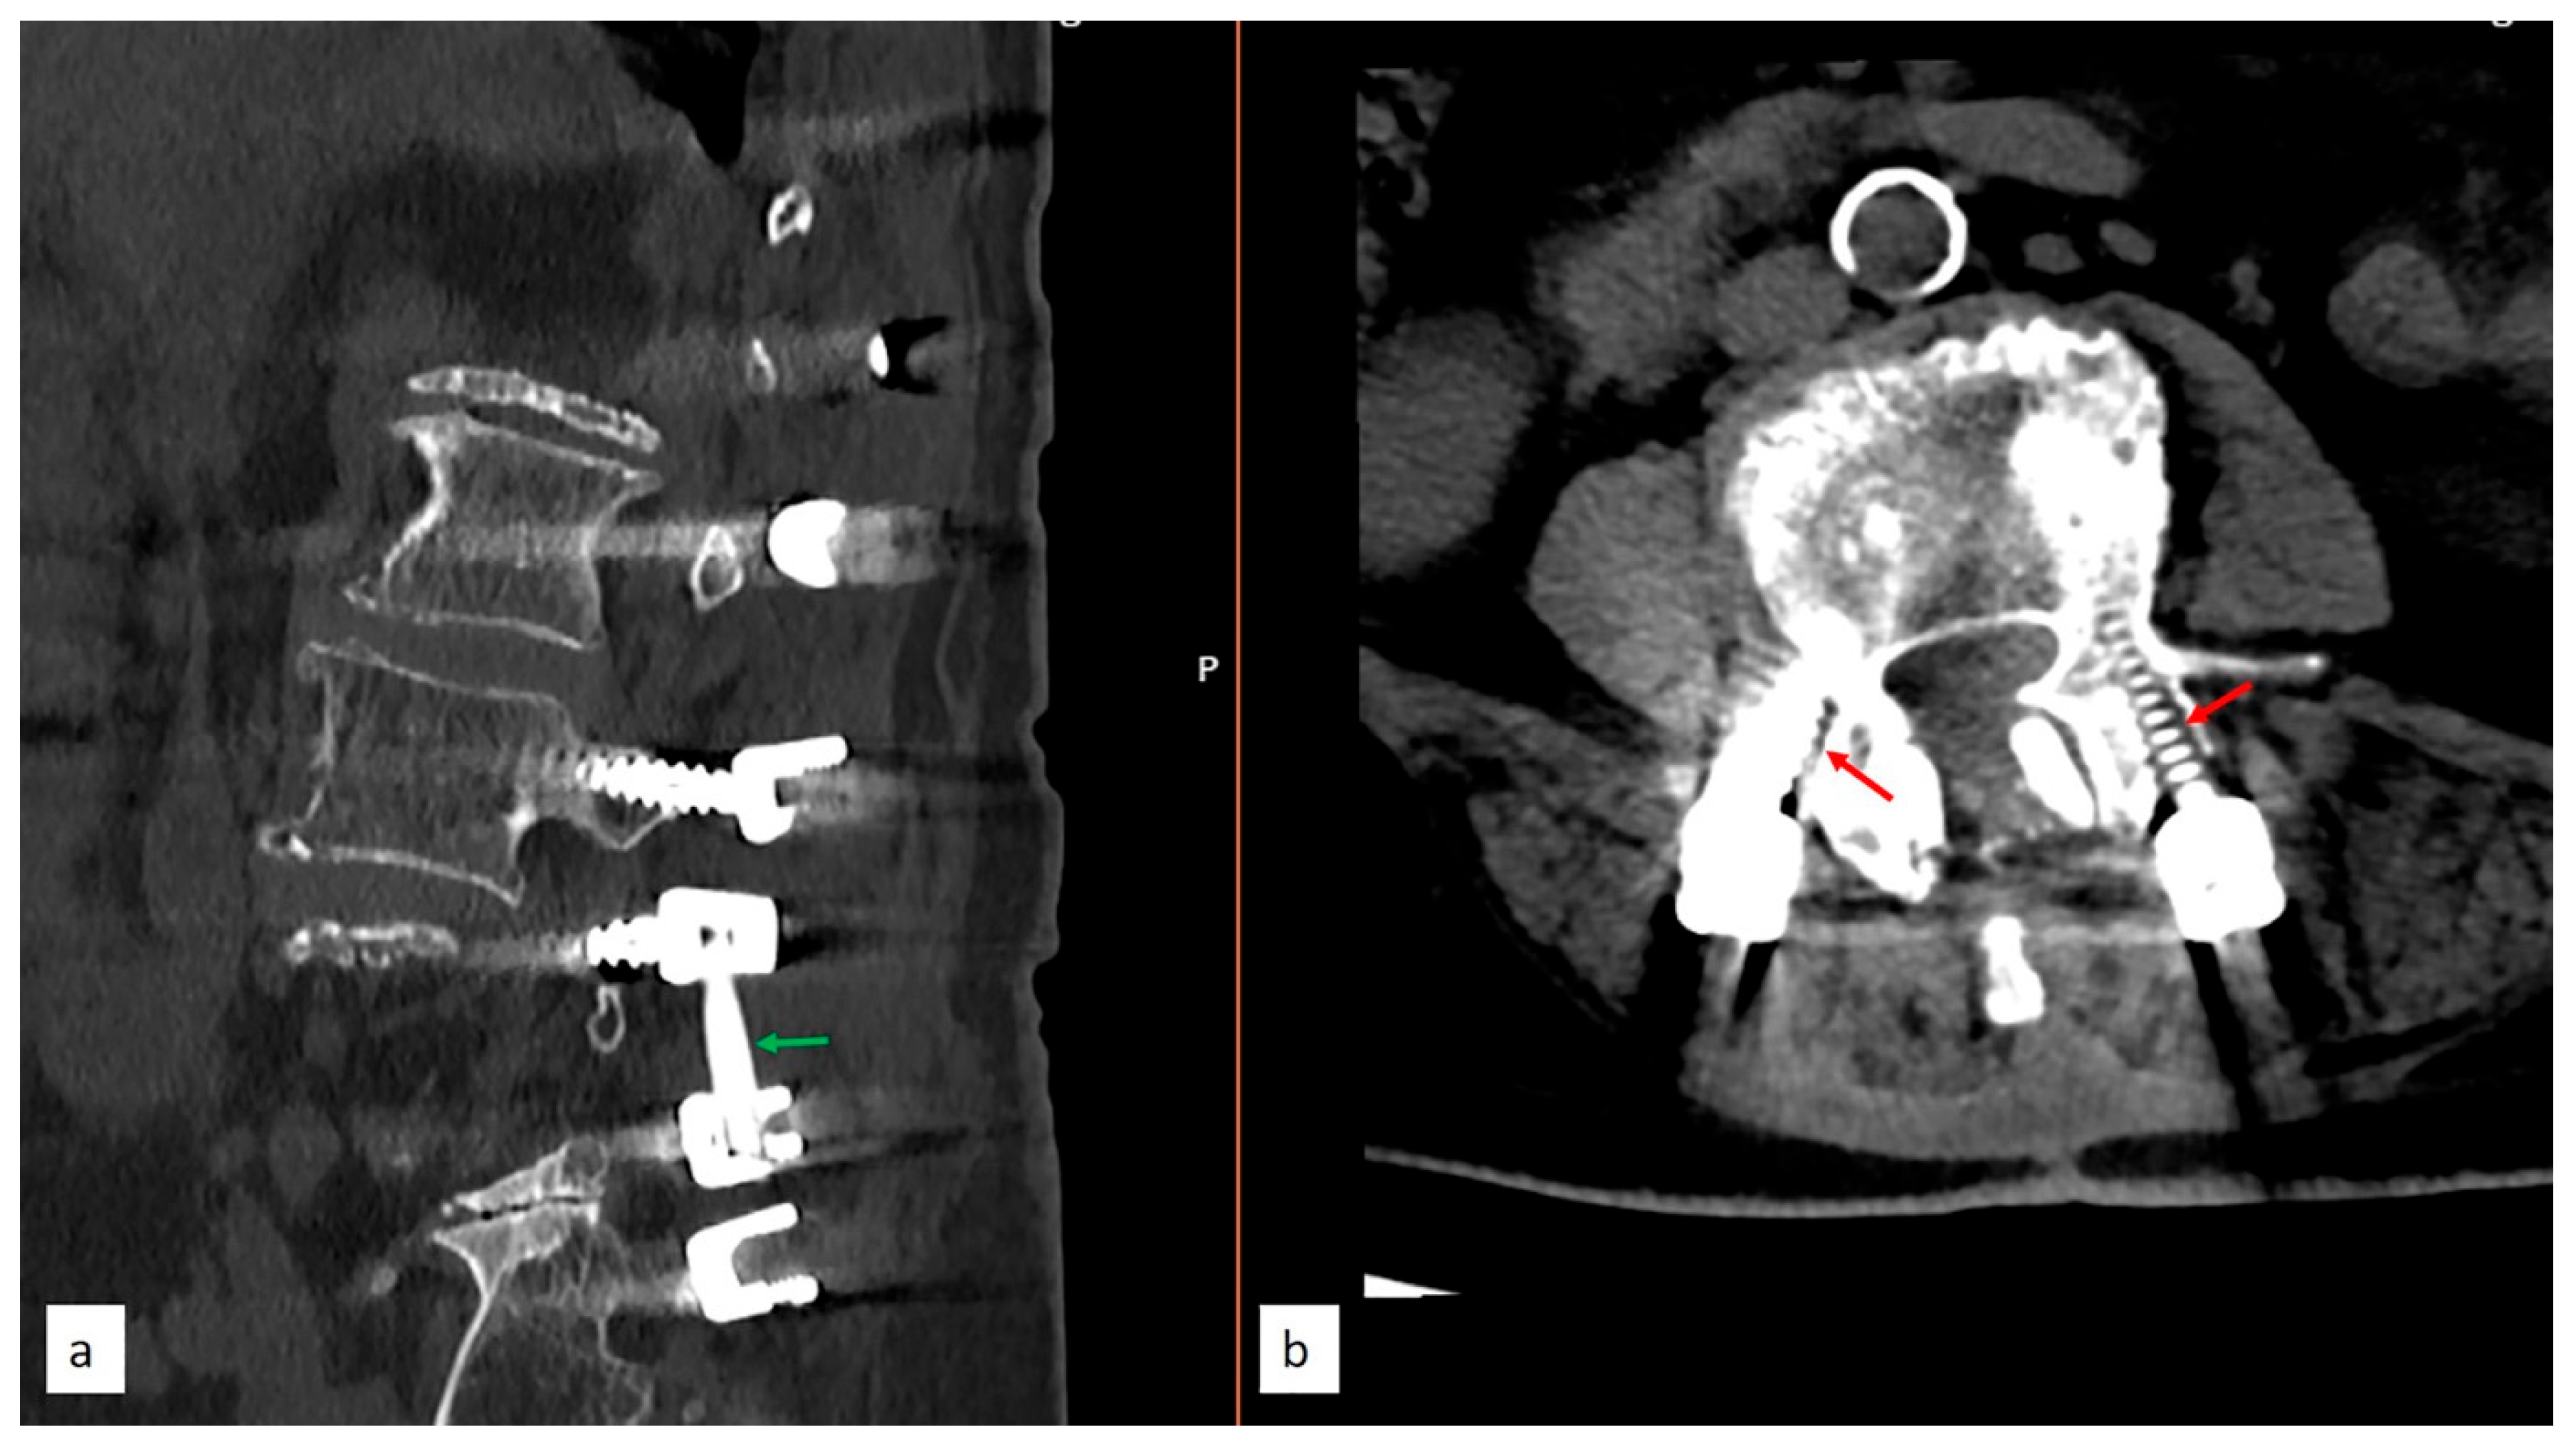

2.3. Radiological Analysis

2.4. Surgical Technique and Nuances